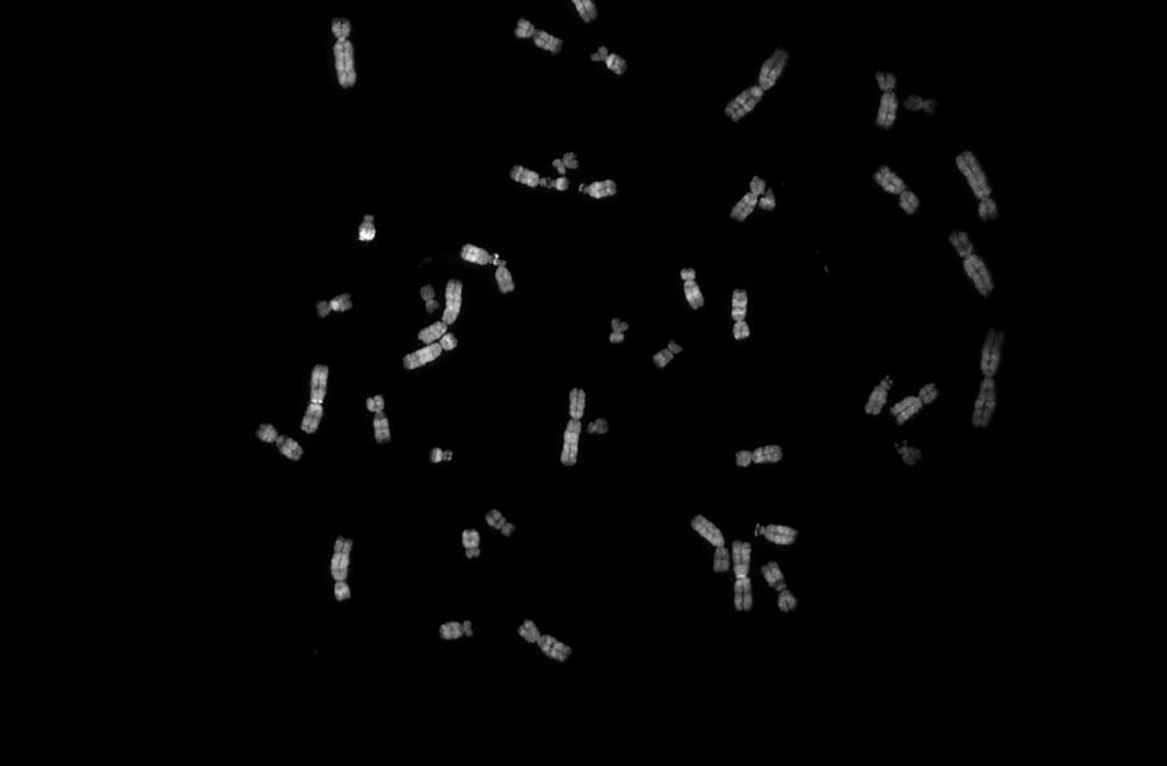

В 1923 году прошлого столетия американский цитолог Теофилус Пейнтер опубликовал работу, в которой заявил, что у человека 48 хромосом. «Ошибка закралась из-за низкого качества препаратов, которые он анализировал. В науке очень с ложно опровергнуть то, что у же опубликовано в авторитетных журналах. Поэтому человечество пребывало в заблуждении относительно числа хромосом еще 30 лет, пока в 1950-х годах две группы ученых, изменив методику подготовки препаратов, не сошлись на том, что хромосом у человека 46», — рассказывает Анна Пендина. Чуть позднее французский врач-педиатр, генетик Жером Лежён пытался найти причину умственной отсталости у детей с синдромом Дауна. «На одной из конференций он услышал, что разработали методику получения метафазных хромосом из фибробластов кожи. Изучив образцы кожи у своих пациентов, Жером Лежён обнаружил, что у них 47 хромосом, а 21-я хромосома представлена тремя копиями вместо двух, — говорит Анна Пендина. — Это позволило понять роль наследственности в этиологии этого заболевания, что я вилось в определенном смысле революцией в науке и медицине. В последующем был сделан целый ряд открытий в области наследственных болезней и состояний».

Благодаря пониманию, что многие заболевания обусловлены изменением в системе хромосом, получила свое максимальное развитие медицинская генетика и клиническая цитогенетика в частности.